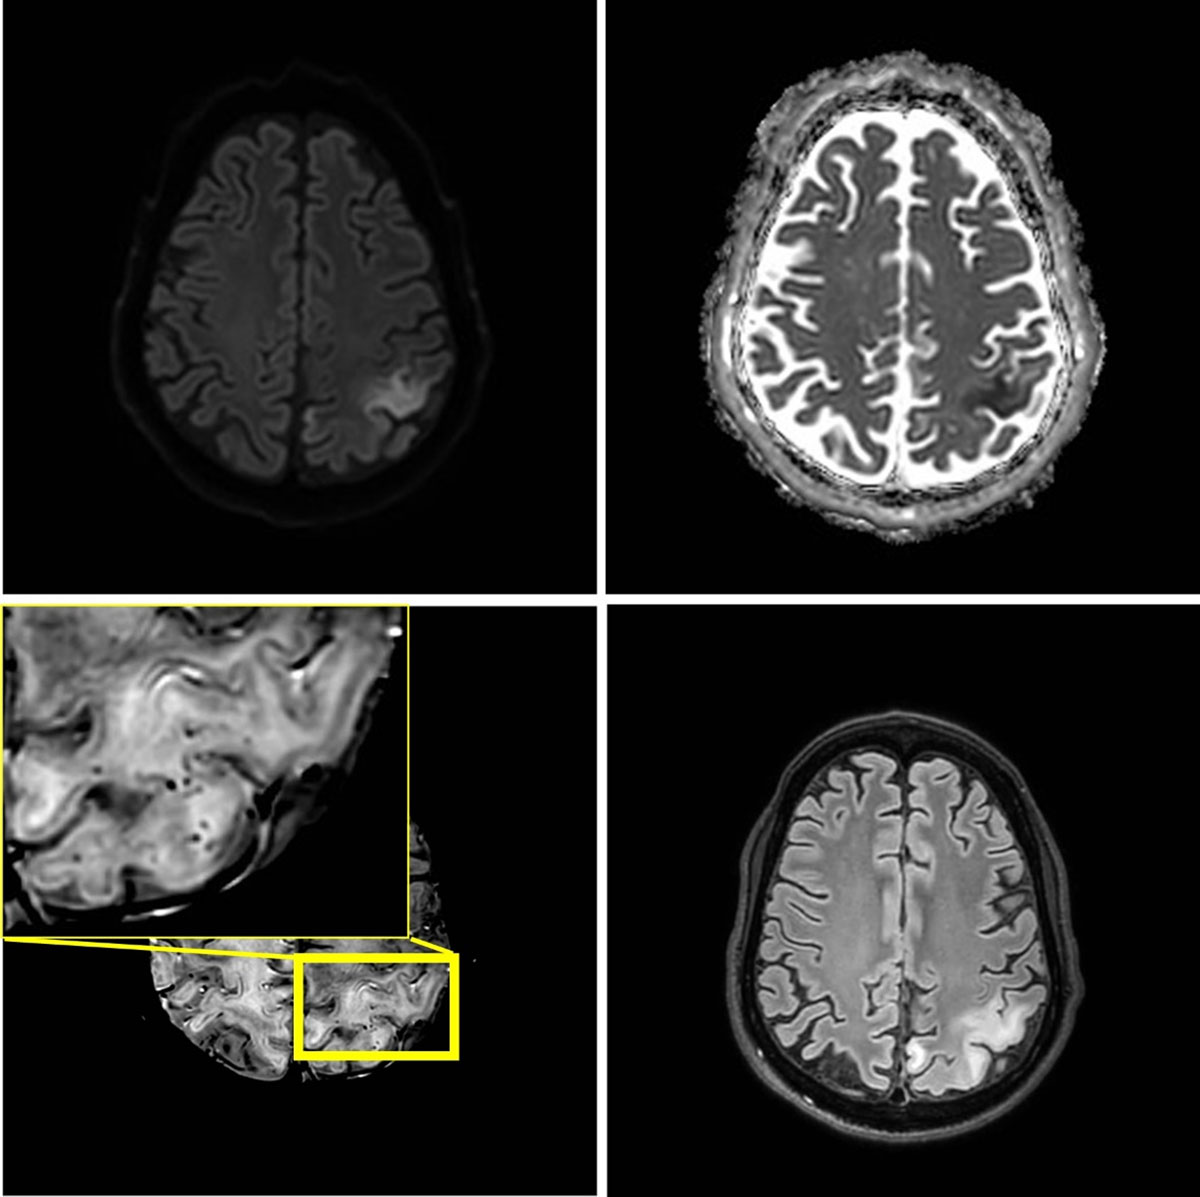

Figure 3

One month later, seven weeks after the initial episode, a third stroke-like event occurred. MRI shows a new area of edema in the left parietal lobe including the postcentral gyrus. The new lesion shows diffusion restriction and juxtacortical microhemorrhages.

After three and seven weeks, two new stroke like-episodes occurred with similar imaging findings respectively in the left occipital region with right hemianopia, and in the left parietal region including the postcentral gyrus with right arm paresis and sensory deficits (Figures 2 and 3). Notably, at seven weeks, microhemorrhages were also present in the acute lesion. Signal abnormalities in previously affected areas nearly normalized, but microhemorrhages persisted.